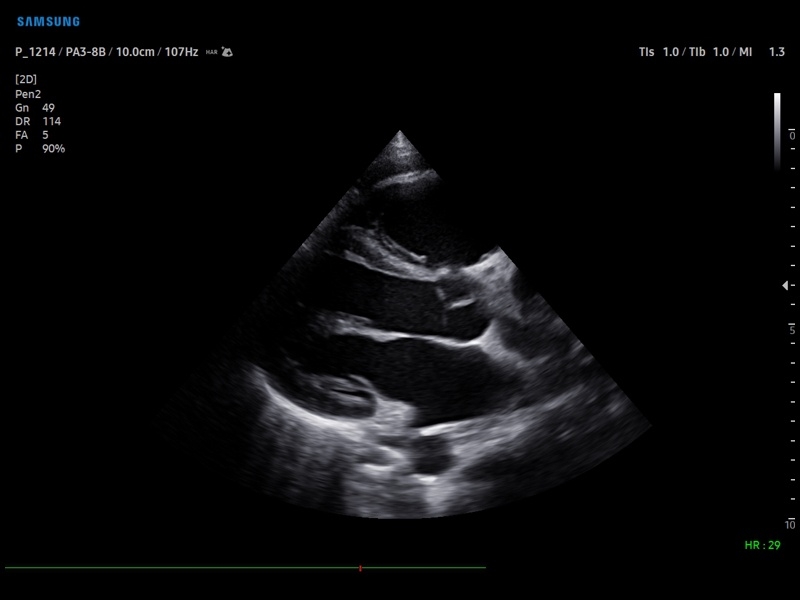

Ультразвуковой сканер V8-RUS является экспертным классом (премиальный уровень) и производится компанией Samsung Medison. Сканер V8 обеспечивает превосходное качество изображения благодаря использованию технологии Crystal Architecture™, которая включает в себя передовое аппаратное обеспечение, монокристальную технологию изготовления датчиков и сложную программную обработку ультразвуковых лучей.

Samsung Medison V8 представляет собой современную ультразвуковую систему, в которой воплощен многолетний опыт компании Samsung в создании эргономичного и интеллектуального диагностического оборудования. Система оснащена передовыми инструментами автоматизации, которые значительно упрощают рабочий процесс и повышают эффективность исследований.

• Кардиология

• Эзофагокардиография